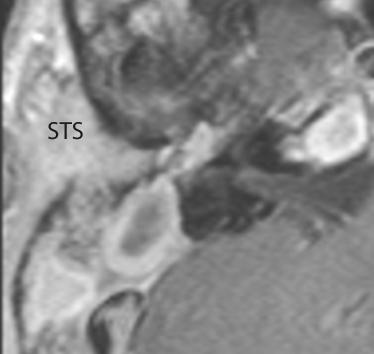

MRI: Anatomically focused axial and coronal images through the temporal bone region and posterior fossa including T1 and T2-weighted acquisitions done with and without gadolinium contrast enhancement and, when indicated, MRV.

There are dural reactive changes or a subperiosteal/epidural abscess along the sigmoid plate of the mastoid displacing the adjacent sigmoid sinus. [Yes/No]